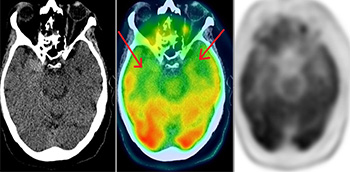

PET/TAC y PET/RM en demencias

El objetivo del Informe es recomendar cuándo es útil el uso de biomarcadores de imagen molecular en los diversos tipos de demencias. Está bien establecida la utilidad de PET/TAC con FDG. Sin embargo, la aparición reciente de nuevos biomarcadores de PET como los...